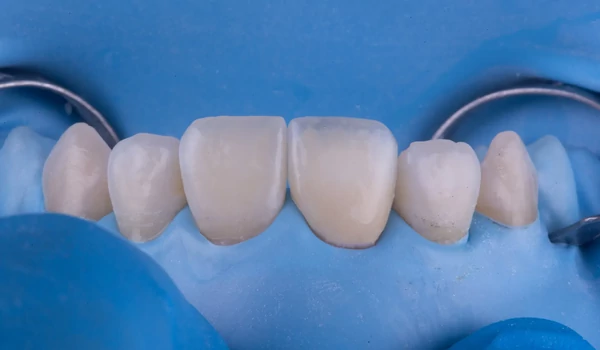

BevezetésA frontfogak traumás törései egyaránt megkövetelik az esztétikum és funkció tökéletes egyensúlyát – mindezt gyakran a páciens érzelmi nyomása alatt. Dr. Koray Kendir esetbemutatója azt szemlélteti, hogyan lehet egy korábban nem megfelelően kezelt centrális metszőt biomimetikus (a természetre emlékeztető) megközelítéssel és Kuraray Noritake termékek segítségével sikeresen rehabilitálni kuraraynoritake.eu. Az eset összefoglalásaEgy 23 éves nőbeteg jelentkezett egy hónappal a trauma után. A sérült 11-es fogon (FDI jelölés) korábban más szakorvos által végzett gyökérkezelést és direkt kompozit felépítést találtak, amely azonban esztétikailag és marginálisan is elégtelennek bizonyult (1. ábra) kuraraynoritake.eu. |

1. ábra. Klinikai helyzet kiinduló pont |